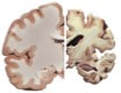

Mass spectrometry (MS) for Alzheimer's

Mass spectrometry (MS) is an analytical technique that measures the masses within a sample.

Novel Alzheimer’s Disease detection assay​ We plan to use mass spectrometry to measure plasma amyloid beta-proteins and amyloid beta- approximate peptides (ABAPs)  to detect cerebral amyloid deposition to pre-screen for detection of Alzheimer's disease using only a blood sample.    Subjects responsive to this biomarker may predictively affirm potential early onset of Alzheimer's, which could then be confirmed by positron emission tomography (PET) scan, as well as the effects of Heterochronic Plasma Exchange in mitigating or remediating key biomarkers of Alzheimer's disease, including cerebral amyloid deposition.